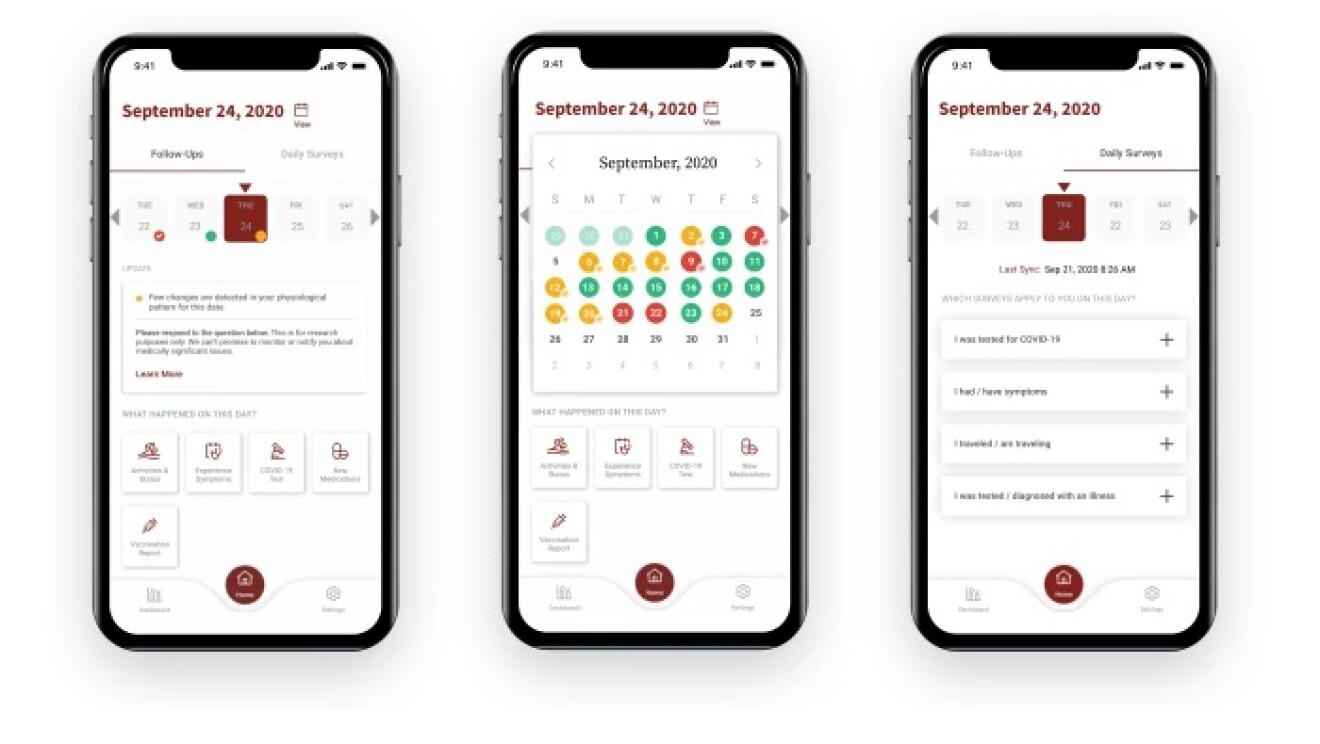

米スタンフォード大学医学部:スマートウォッチを使った診断用アラームシステムを開発

スタンフォード大学医学部ヘルスケア・イノベーション・ラボの研究者らは、COVID-19感染症と闘うための兆候をとらえるスマートウォッチ・アプリを開発しました。このアプリは、個人の安静時の心拍数と歩数の変化を検出するアルゴリズムを搭載しており、パイロット試験では新たに感染した人が症状を自覚する10日前に警告を発することに成功するなど、初期段階で良好な試験結果を得ています。

このアプリは次の研究段階に入っており、スタンフォード大学のチームは、COVID-19の兆候をリアルタイムで検出する能力を高めるため、1,000万人を目標に試験への参加者を募集しています。このスマートウォッチを利用した早期発見システムは、AWSプロフェッショナルサービスチームによるデータ処理パイプラインに関する支援を受けてAWS上に構築されました。

スタンフォード大学医学部 遺伝学分野教授 兼 学科長のMichael Snyder(マイケル・スナイダー)博士は、次のように述べています。「身に着けられるデバイスを用いた継続的な検診により、現在の検査の壁を克服するための拡張的な診断ソリューションが提供されること、また、より多くの研究者にデータへのアクセスを拡大することで、人々の健康を向上させる新たな発見に貢献できることを期待しています。今後もクラウドを活かして、可能性の限界に挑戦していきたいと思います」